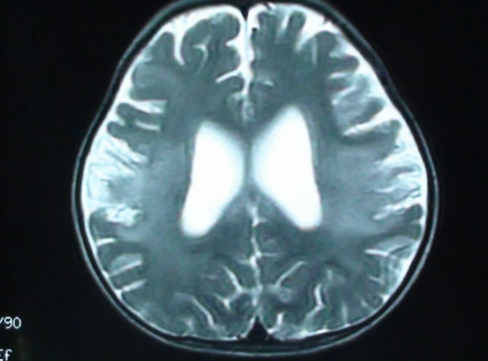

美国学者发现脑胶质母细胞瘤复发的原因